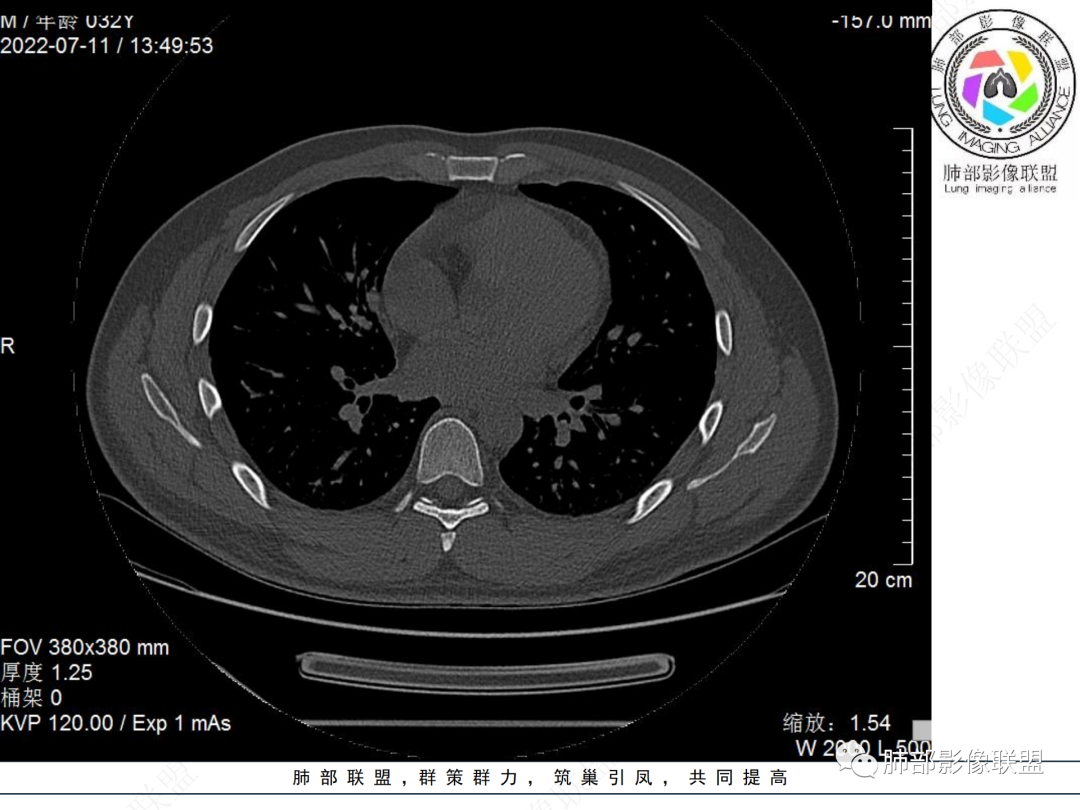

左肺下叶后基底段开口处结节,边缘光滑清楚,没有增强扫描,年轻男性患者痰血三天,考虑1.良性病变:腺瘤、错构瘤、平滑肌瘤

2.恶性:类癌、粘液表皮样癌。

左肺下叶外后基底段气管内见结节状影,边缘部分清晰。考虑错构瘤,待排恶性病变。

左肺下叶气管内外占位病变,咯血病史,考虑类癌,粘表待排。

青年男性,左肺下叶后基底段支气管开口软组织结节,边缘光整,气管镜提示质软,易出血,考虑类癌

左肺下叶后基底段开口处结节,边缘光滑清楚,年轻患者考虑鳞癌或腺样囊腺癌

左肺下叶气道腔内占位,远端无花花草草,疾病谱:鳞,类癌,粘表,腺样囊腺癌,小,无增强,不好判断,临床咯血,选类癌。

大支气管腔内结节,考虑类癌

左肺下叶后基底段开口处结节影,边缘光滑,患者年龄较小,首选类癌

男性,咳血左肺下叶支气管腔内结节影,没有阻塞性炎症,考虑类癌,鳞癌

年轻男性,支气管内结节,首先类癌

左肺下叶后基底段开口处腔内见壁结节,花生米样,宽基底,补充增强及矢状位重建,确定我无向壁外突破浸润生长,另见强化的特点,临床触之易出血,类Ca可能性大。

年轻男性,支气管腔内占位,边缘尚平整,年轻人,首先类癌,鉴别错构

年轻男性,咳血,左肺下叶后基底段支气管腔内结节,边缘光滑,首先考虑青年三件套,类癌大于粘液表皮样癌,支气管镜质软,触之易出血,鉴别血管瘤,平滑肌瘤

左肺下叶后基底段开口部结节,密度较均匀一致,边缘较光整,目测密度偏低,支气管镜示:质软、触之易出血,考虑恶性,类癌。

支气管腔内结节,有蒂与支气管壁连接,考虑良性病变可能性大,支气管错构瘤  血管瘤一类的

左肺下叶后基底段支气管腔内结节,有蒂,容易出血,先考虑良性病变,肉芽组织型血管瘤,与类癌鉴别。

青年男性,左肺下叶后基底段支气管开口软组织结节,边缘光整,气管镜提示质软,易出血,考虑恶性类癌

左肺下叶后基底段开口处结节影,边缘光整,年轻患者,伴咯血,考虑鳞癌,类癌不能排除